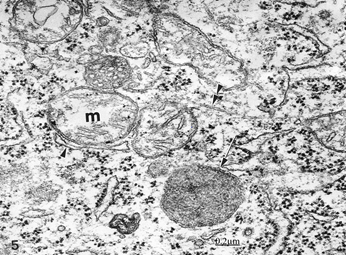

We found swollen and ischemic neurons and glial cells leading to nerve cell death types, such as apoptosis, oncosis, autophagic cell death leading to necrosis (Figure 5).16, 17 Astrocyte exhibiting apoptotic cell death type showing apoptotic bodies in nucleus and cytoplasm (Figure 6). Morphopatological changes of dendrites17 and dendritic spines18,19 are observed. The dendrites show a beaded shape, vacuolization, edematous mitochondria and cytoskeletal disruption (Figure 7). Dendritic postynaptic spines appear swollen and contain an atrophic spine apparatus. They are observed making axospinodendritic synapses (Figures 8&9).

Figure 5 Brain trauma, subdural hematoma- Light microscopy section showing dark necrotic neuron (N) and oligodendroglial cell (OL) in the vicinity of an edematous astrocyte (A). Note the degenerated myelinated axons (MA).